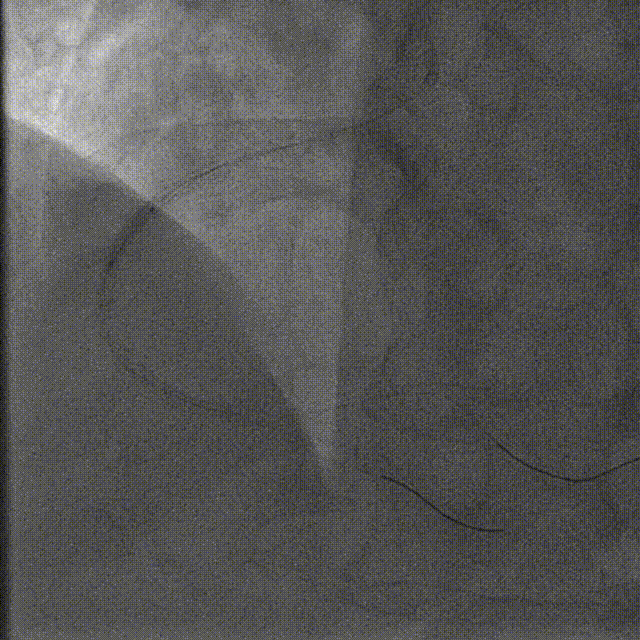

在Telescope™导引延长导管辅助下,选择2.5*12mm高压球囊、2.75*15mm高压球囊于支架内后扩张

在Telescope™导引延长导管辅助下,选择3.0*15mm高压球囊于支架内后扩张